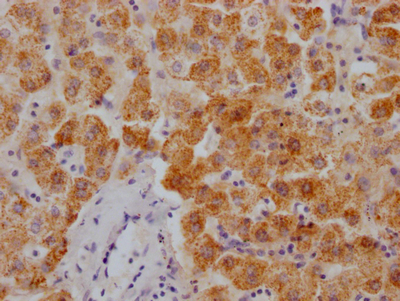

Immunohistochemistry of paraffin-embedded human colon cancer using CSB-PA010418PA10nphHU at dilution of 1:100